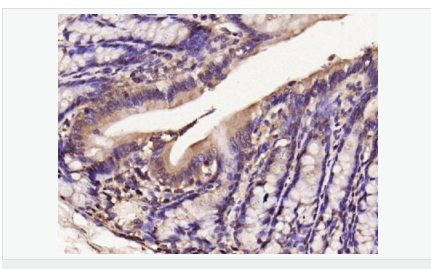

| 產(chǎn)品介紹 | Nitric oxide (NO) is an inorganic, gaseous free radical that carries a variety of messages between cells. Vasorelaxation, neurotransmission and cytotoxicity can all be potentiated through cellular response to NO. NO production is mediated by members of the nitric oxide synthase (NOS) family. NOS catalyzes the oxidization of L-arginine to produce L-citrulline and NO. Two constitutive isoforms, brain or neuronal NOS (b or nNOS, type I) & endothelial cell NOS (eNOS, type III), and one inducible isoform (iNOS, type II), have been cloned. All NOS isoforms contain calmodulin, nicotinamide adenine dinucleotide phosphate (NADPH), flavin adenine dinucleotide (FAD), and flavin mononucleotide (FMN) binding domains. Nitric oxide synthase is expressed in liver, macrophages, hepatocytes, synoviocytes, stimulated glial cells and smooth muscle cells. Cytokines such as interferon-gamma (IFN), tumor necrosis factor (TNF), interleukin-1 and -2, and lipopolysaccarides (LPS) cause an increase in iNOS mRNA, protein, and activity levels. Protein kinase C-stimulating agents exhibit the same effect on iNOS activity. After cytokine induction, iNOS exhibits a delayed activity response which is then followed by a significant increase in NO production over a long period of time. Human iNOS is regulated by calcium/calmodulin (in contrast with mouse NOS2). Function: Produces nitric oxide (NO) which is a messenger molecule with diverse functions throughout the body. In macrophages, NO mediates tumoricidal and bactericidal actions. Also has nitrosylase activity and mediates cysteine S-nitrosylation of cytoplasmic target proteins such COX2. Subunit: Homodimer. Binds SLC9A3R1. Tissue Specificity: Expressed in the liver, retina, bone cells and airway epithelial cells of the lung. Not expressed in the platelets. Similarity: Belongs to the NOS family. Contains 1 FAD-binding FR-type domain. Contains 1 flavodoxin-like domain. SWISS: P35228 Gene ID: 4843 Database links: Entrez Gene: 4843 Human Entrez Gene: 18126 Mouse Omim: 163730 Human SwissProt: P35228 Human SwissProt: P29477 Mouse Unigene: 709191 Human Unigene: 2893 Mouse Unigene: 10400 Rat Important Note: This product as supplied is intended for research use only, not for use in human, therapeutic or diagnostic applications. 合成與降解(Synthesis and Degradation) 催化生物體內一氧化氮(NO)生成的酶。分神經(jīng)型一氧化氮合成的酶(nNOS or NOS-1)、誘導型一氧化氮合成的酶(iNOS or NOS-2)、內皮型一氧化氮合成的酶(eNOS or NOS-3)。 |